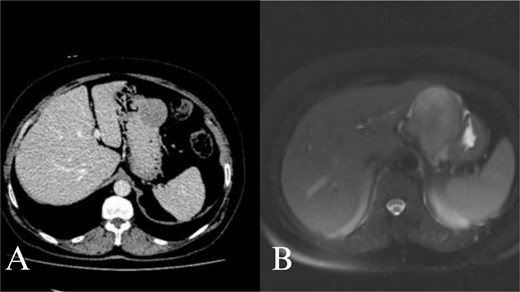

Abdominal CT and MRI images. Contrast enhanced axial tomography revealed a hipodens mass with smooth boundary located at the greater curvature of the stomach. Axial T1 weighted MRI revealed a hypointense, moderate contrast enhancing mass with smooth boundary located at the gastric antrum.

A 70-year-old female was referred to our hospital because of a 6-month history of abdominal discomfort and epigastralgia. Admission vitals, physical exam, routine blood tests, and tumor markers showed normal results. Upper GI endoscopy revealed one protruding lesion 8 cm in size at the lesser curvature of the gastric body. Fine needle aspiration showed chronic inflammation without malignancy. Computed tomography (CT) of the upper abdomen showed a mass originating from the greater curvature of the stomach (Fig. 1A). With suspected GIST, we proceeded with surgery. At laparotomy, an 8 × 7 × 7 cm mass was found at the greater curvature and resected en-bloc with gastric wedge resection. Microscopically, the tumor consisted of spindle cells, positive for S-100 protein and vimentin, while negative for CD 117, CD 34, β-catenin, SMA, synaptophysin, chromogranin, and desmin, consistent with schwannoma (Fig. 2A and B). Postoperative recovery was smooth, and the patient was discharged on Day 5. At 2 years, the patient remains healthy and recurrence-free.

A 66-year-old female with a history of abdominal discomfort, epigastralgia, and anemia for 10 months was admitted. The results of admission showed good vital status and general condition except for a low level of hemoglobin at 7.0 g/dL and hematocrit at 23.1%. Upper GI endoscopy showed a submucosal mass at the greater curvature of the antrum. Biopsy cytology demonstrated spindle cell morphology and thus suspected GIST. CT and magnetic resonance imaging (MRI) revealed the mass at the gastric antrum with smooth-bounded margins without lymphadenopathy (Fig. 2B). Laparotomy showed a mass measuring 6 × 6 × 7 cm. En-bloc excision of the mass had been done with subtotal gastrectomy and Roux-en-Y reconstruction. This was histologically proven through positive S-100 and vimentin markers that are negative for CD 117, CD 34, and other markers and confirmative of schwannoma. She did well post-operatively and was discharged on Day 7. She remains well at 18 months follow-up with no recurrence.